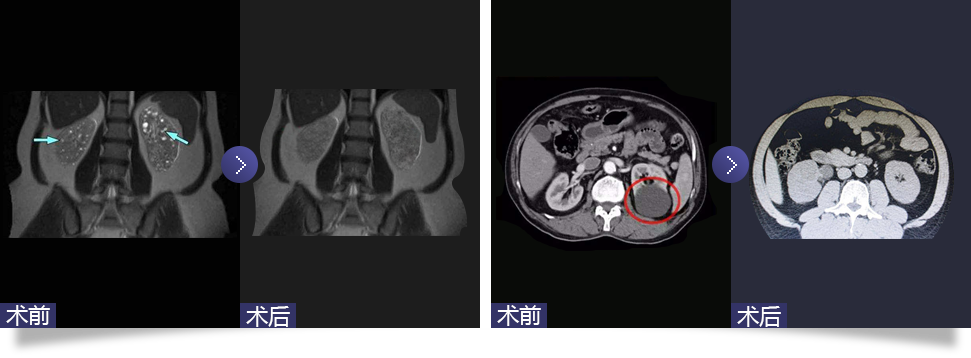

腹腔镜下肾囊肿去顶减压术

Laparoscopic renal cyst deparization and decompression

随着腹腔镜技术在泌尿外科领域的广泛应用,腹腔镜下囊肿去顶减压术成为治疗肾囊肿的主要方法。通过腹腔镜下用超声刀切开腹膜,伤口为1.5-2.0cm,分离肾周脂肪,找到充分暴露的肾囊肿壁边缘,切开囊肿壁并吸净囊液。